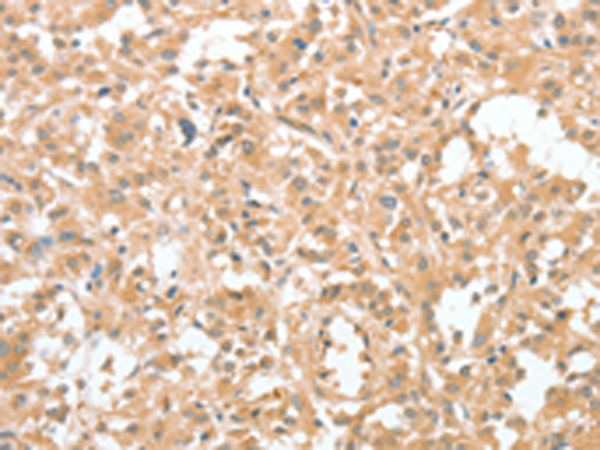

分类: 科研抗体货号: P08178别名: RBP6; CRABP-II应用: IHC反应种属: Human, Mouse, Rat